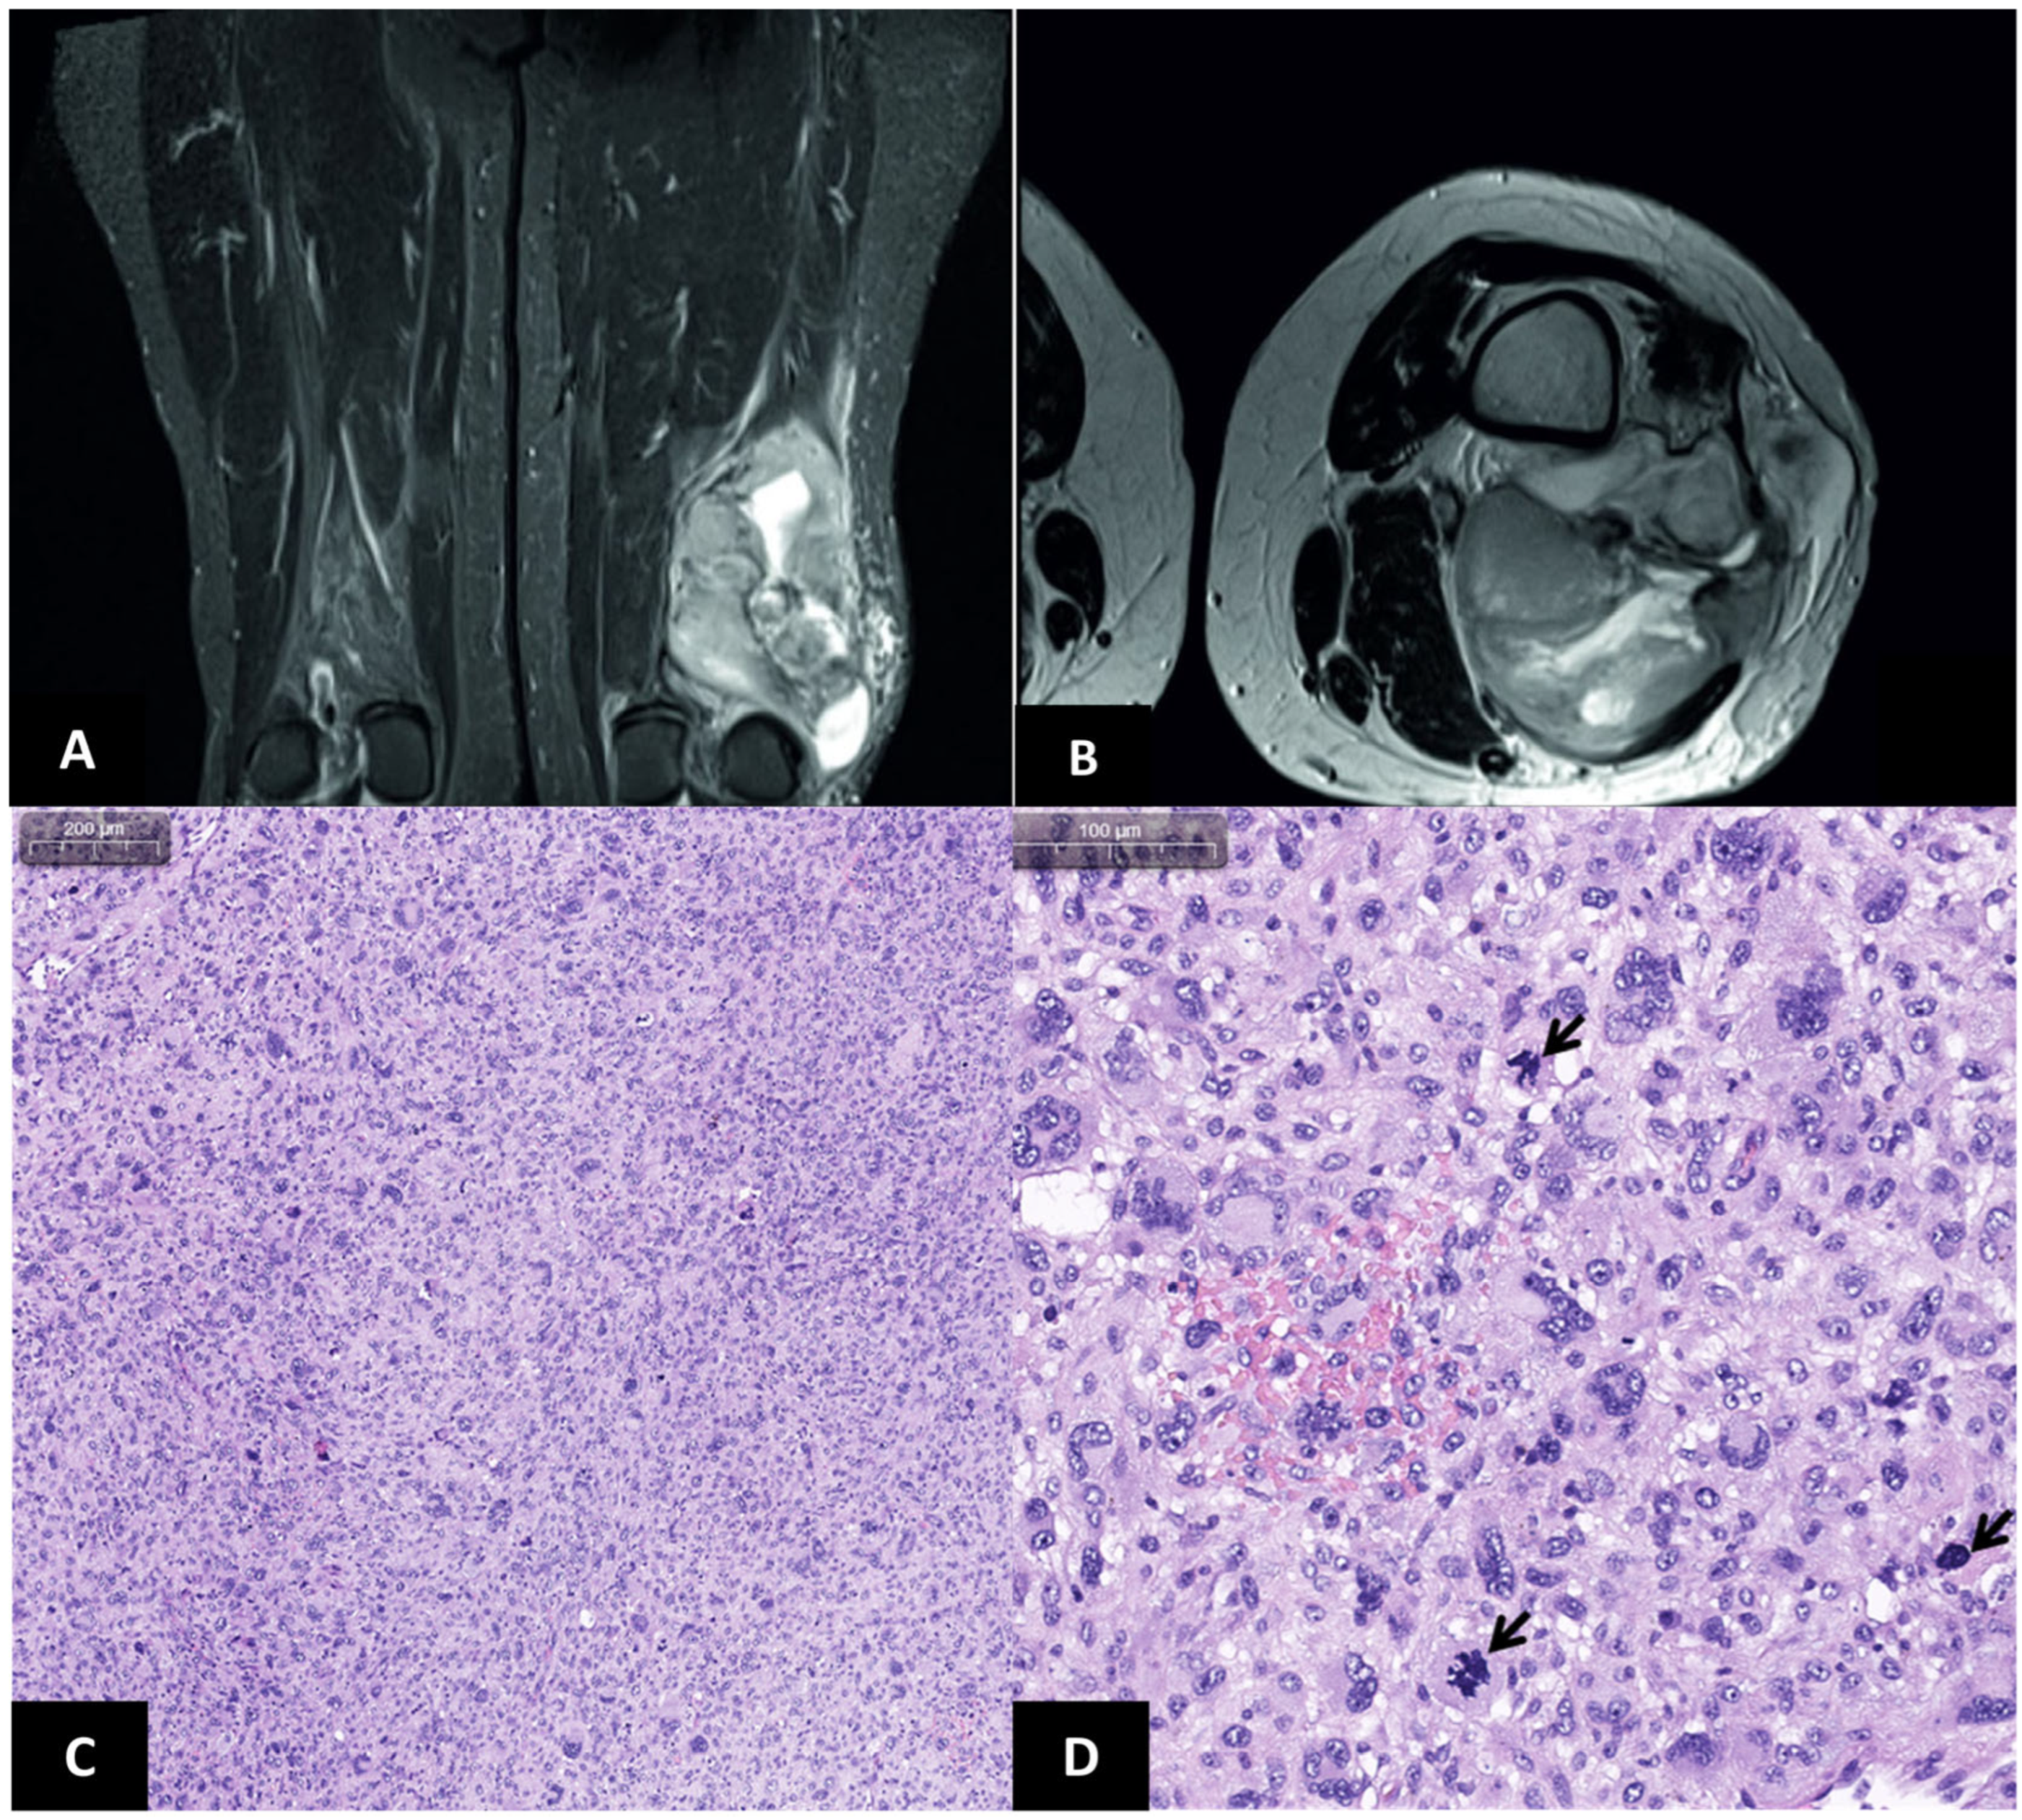

2. Case Report